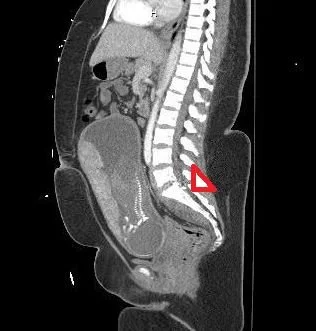

Hint; the image below points to the problem; and yes she is 23 wks pregnant

Our patient has an injury at the level of L5-S1 with a fracture of the L lateral vertebral body of L5 and R S1 lamina with retained fragments in the spinal canal and a large osseous fragment in the R S1 neural foramen. She was neuro intact but did not move her legs secondary to pain, most likely from bony fragments compressing the sacral nerves.

final position of the bullet after traversing L5.